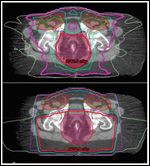

Examples of differential sparing of bladder and femoral heads between intensitymodulated radiation therapy (top) and 3-dimensional (bottom) plans.

RTOG 05-29 is a prospective phase II efficacy trial utilizing IMRT in the treatment of anal canal cancer.[39] All patients received concurrent 5FU and MMC. In this study, IMRT was delivered by “dose painting,” in which different target volumes are treated concurrently but different-sized radiation fractions are used for different target structures, which is achievable with IMRT. The doses prescribed to elective nodal areas depended on the stage of disease, and the total dose to gross disease ranged from 50.4 to 54 Gy. As an example, the patient depicted in Figures 2-9 with T2N2M0 disease might have received 1.5 Gy/day (to a total of 45 Gy) to the uninvolved (elective) inguinal and upper pelvic regions, 1.68 Gy/day (to a total of 50.4 Gy) to an involved right pelvic lymph node (which measured ≤ 3 cm), and 1.8 Gy/day (to a total of 54 Gy) to the gross anal canal tumor.